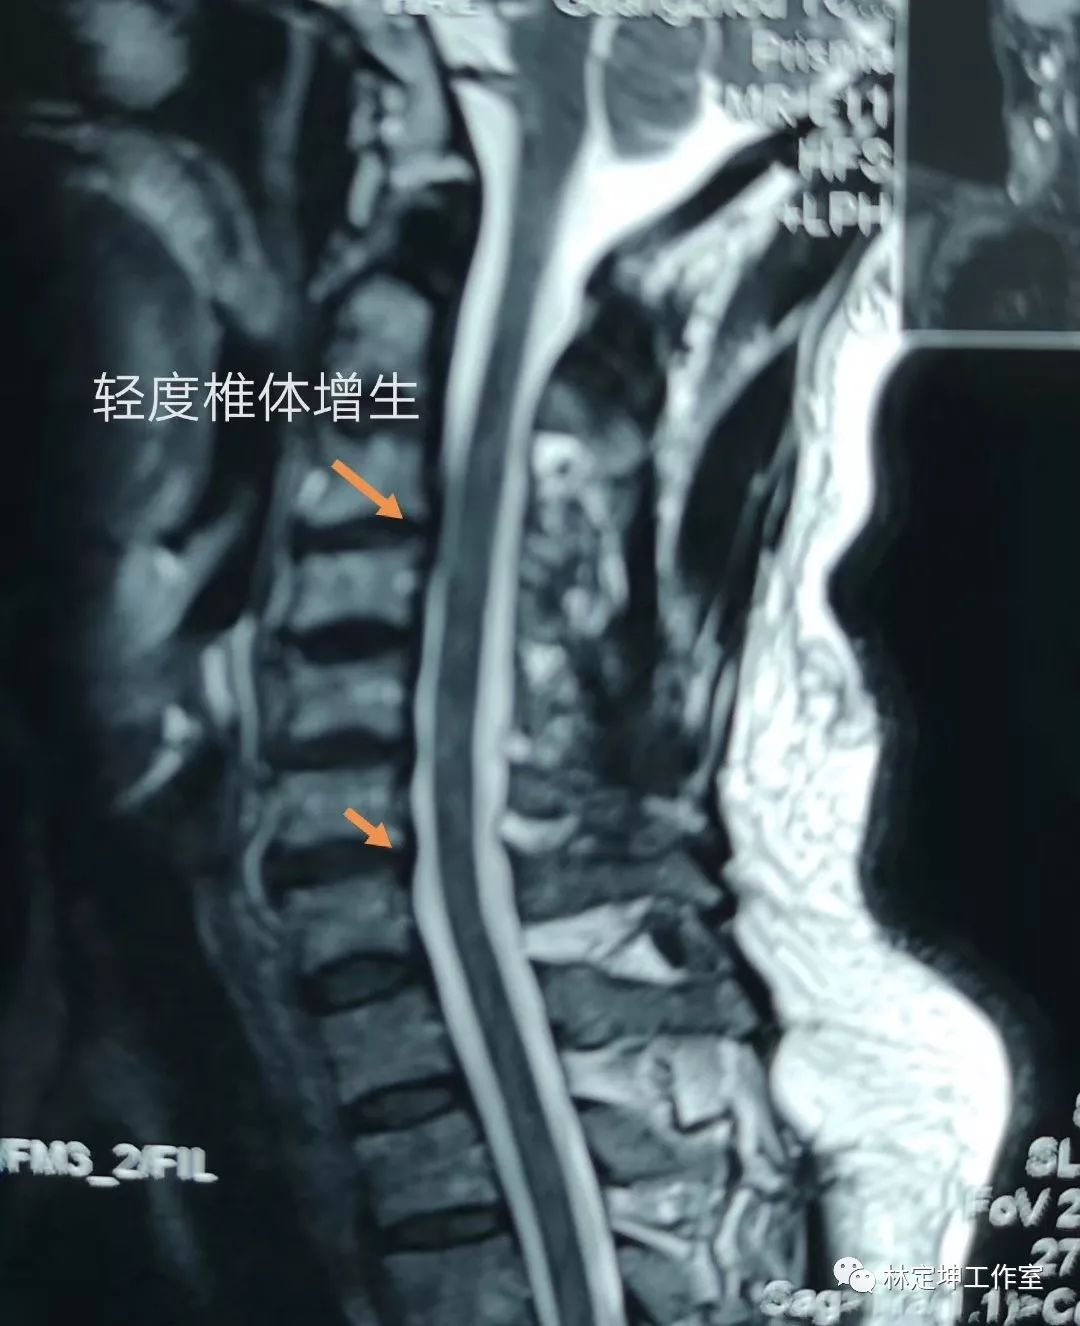

颈部的MR显示颈3、4椎间盘轻度突出,椎间隙后缘轻度增生,压迫硬膜囊,脊髓没有受压。

张先生的颈椎MR

这种影像学的改变,在中年人中是非常常见,大多数仅有颈部的不适。而张先生却这样难受!因为他的病不是增生引起的,也不是脊髓受压引起的,而是他的颈3、4椎节和6、7椎节的小关节错位导致的。

这种错位,从影像上看不太明显,但手诊时却很明显能摸出来。颈椎小关节囊中,有丰富的交感神经,错位会引起诸多症状。